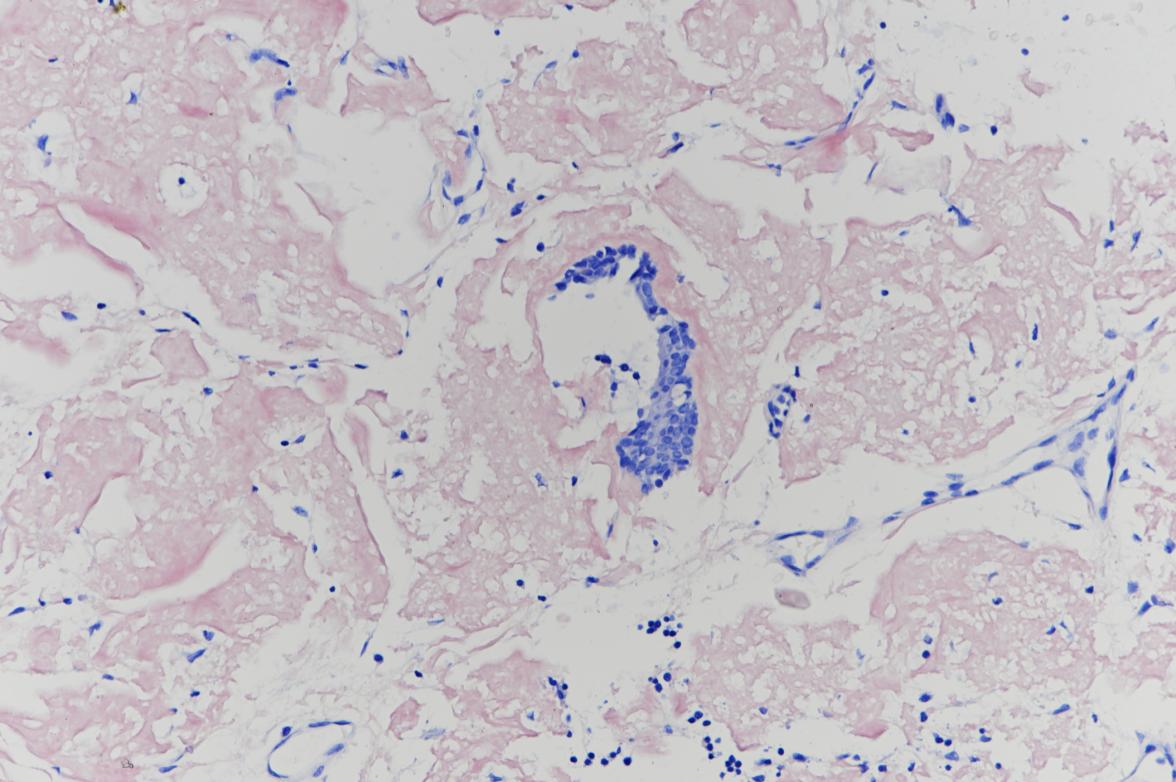

2.补充报告(2015-10-16):(支气管)破碎粘膜上皮伴弥漫性淀粉样物质沉着。见图5

4. 特染:刚果红(+),见图6,网染(示网状纤维较少),AB(-),PAS(-)

图5

图6